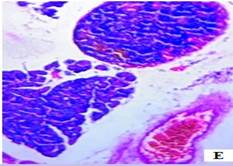

The histopathological studies of the pancreatic tissues are shown in (fig. 3). Normal rats showed the normal architecture of the pancreas with the preserved islet of Langerhans cells (fig. 3A). Induction of diabetes using Streptozotocin resulted in hyalinization of islets of Langerhans cells with focal mild degenerative changes, mild fibrosis, dilated and congested vessels along with focal chronic inflammatory cell infiltrate in diabetic rats (fig. 3B). HFT control rats showed mild edema of islets of Langerhans cells, thick-walled and congested vessels, focal lymphocytic infiltrate exhibiting focal edematous changes (fig. 3C). The abnormal histopathology of the pancreas due to Streptozotocin-induced diabetes was reversed in the Glibenclamide, and EAFBN treated diabetic animals.

The recovery of standard Glibenclamide treated group was evident as near normal architecture with preserved islet cells and mild edema (fig. 3D). The resulted in EAFBN (100 mg/kg, 200 mg/kg & 400 mg/kg) treated groups mild hyalinization islets of langerhans cells with focal mild degenerative changes when compared to untreated diabetic rats. It can be noted that the islets of langerhans cells regenerated in the treatment groups (fig. 3E,3F& 3G).

Fig. 3: Histology of control and treated rat pancreas of antidiabetic studies. A) Control rat, B) Diabetic control, C) HFT control, D) Standard, E) EAFBN (100 mg/kg), F) EAFBN (200 mg/kg) and G) EAFBN (400 mg/kg)